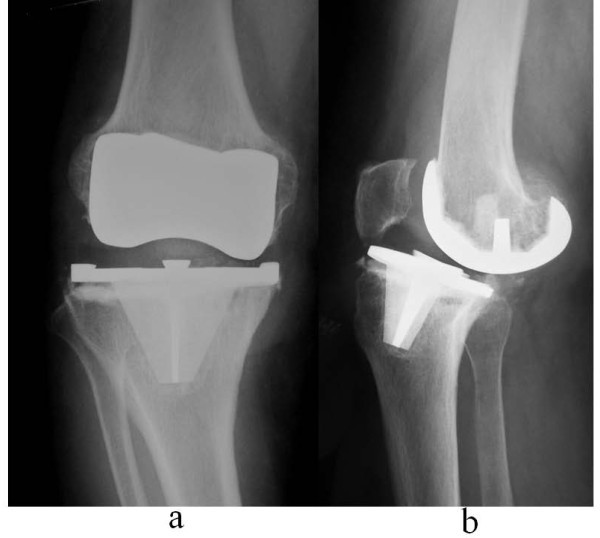

10

Q

CR TKA:

1. What is this prosthesis?

2. What is the design category and feature of this prosthesis?

3. What is the advantages of this type of prosthesis?

4. What is the disadvantages of this type of prosthesis?

A

1. Cruciate-retaining total knee arthroplasty.

2. Least constrained type of TKA, where ACL is removed, PCL is retained. On lateral view, can appreciate pegs instead of a box shape for the retained PCL, PE insert is also more flat to allow the femur to roll back onto the posterior part of bearing.

3. Advantages: i) Retaining PCL allows more bone conserving. ii) Keeping PCL helps to regulate flexion stability and keep flexion gap smaller. iii)Allows more consistent joint line restoration due to ii. iv) Allows more propioception feedback.iii) PCL tension influences femoral rollback, which is the progressive posterior change in femoral-tibial contact point as the knee moves into flexion.

4. Disadvantages: i) Harder to balance with severe deformities (avoid in varus >10 degs, valgus >15 degs). ii) Tight PCL in flexion will lead to increased PE wear. iii) Increase PE wear, increase particle debris, causing osteolysis, leading to dysruption of PCL from bony attachments, resulting in knee instability and repetitive subluxation. iv) Paradoxical forward sliding as knee flexes. PCL prevents posterior translation of the tibia relative to the femur but with ACL gone, tibia can still slide forward, causing sliding wear on PE insert.

11

CS TKA:

1. Posterior stabilised TKA.

2. Cruciate retaining TKA, has spine and cam mechanism in the posterior aspect of the knee, the cam is part of the femoral component between the two posterior femoral condyles, the PE insert has a post which the cam engages onto during flexion thus preventing anterior translation of the femur on the tibia (a function typically by PCL), no posterior roll back as like a normal knee as cam and post control rollback, PE inserts are more dished/congruent to the femoral condyle shape.

3. Advantages: i) Allows easier balancing in severe coronal deformities as ACL and PCL removed (balancing only required in one plane). ii)There is controlled flexion kinematics with spine and cam mechanism, so less sliding wear.

4. Disadvantages: i) Risk of dislocation due to femoral cam jump when flexion gap is too loose and with any varus/valgus stress applied when knee is flexed, thus allowing femoral cam to rotate in front of the post and rests in front of it. ii) Patella clunk syndrome due to scar tissue getting caught in the box. ii) Tibial post wear and breakage. iii) More bone is removed from middle of distal femur. iv) Flexion gap is bigger as PCL is removed, to in order to balance the extension gap additional distal femur is removed and so causing joint line elevation and subsequently patella baja